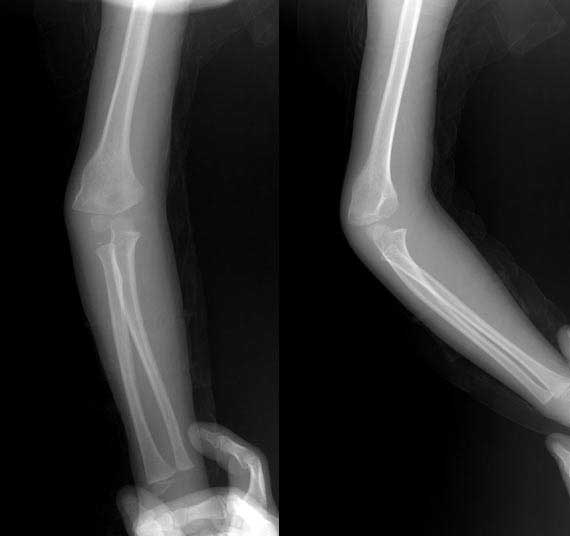

肱骨青枝骨折累及干骺端,干骺端形态不规则。

肱骨髁上青枝骨折!!

肱骨髁上骨折,侧位不标准.

髁上外侧骨皮质彭出,骨皮质连续,肘关节内翻,软组织未见肿胀。内髁小。

印象:陈旧性髁上骨折。

应该是肱骨髁上陈旧性骨折。

如果是新鲜骨折,这么明显的髁上骨折其邻近的软组织一定肿胀的特别厉害,本例骨折处后外侧的软组织根本就没有肿胀。故不支持新鲜骨折。

肱骨青枝骨折累及干骺端

我觉得 肱骨小头中心未和桡骨纵轴再一条直线上